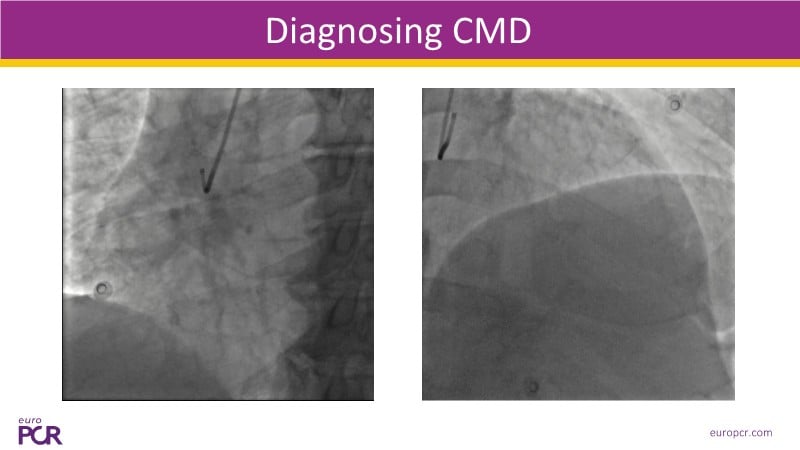

Discover the latest on managing coronary microvascular dysfunction (CMD) with insights from EuroPCR 2025. This session explores how physiology testing helps identify CMD endotypes in the cathlab and highlights the limitations of ETT for patients experiencing angina or dyspnea at rest. Learn about the A-FLUX coronary sinus reducer: a newly designed device optimised for ease of use and symptom relief. With a mechanism of action based on reducing microvascular resistance, this therapy is emerging as a safe, simple, and effective option. The upcoming SERRA-I feasibility study will further strengthen the clinical evidence for CMD patients with persistent angina or angina-like symptoms.

- To recognise the importance of diagnosing coronary microvascular dysfunction